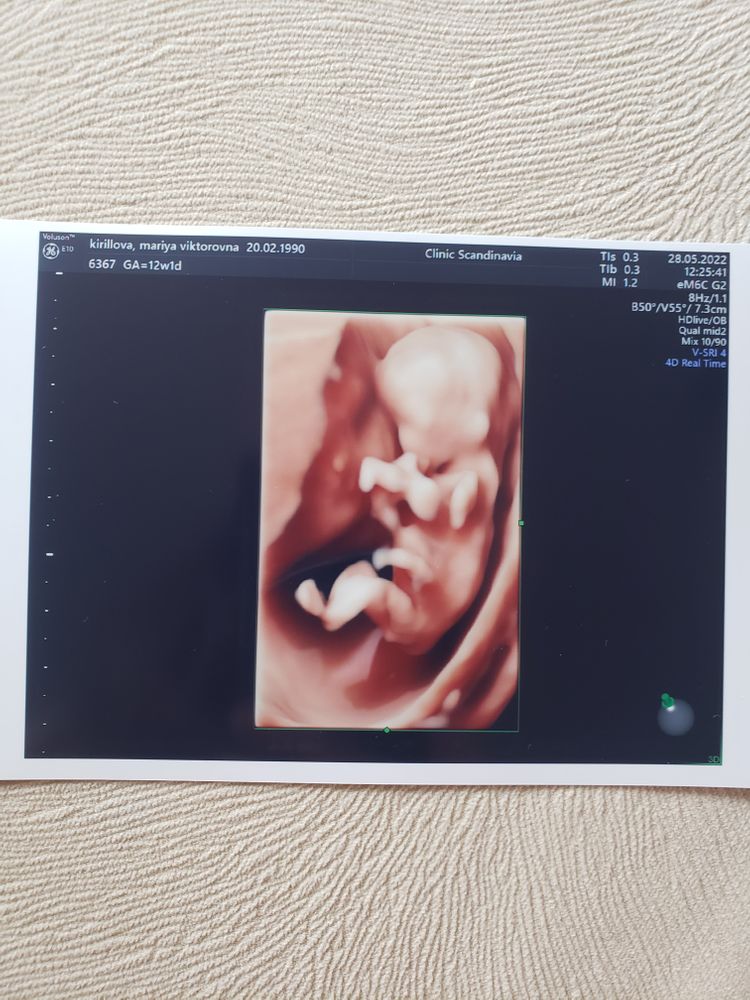

1 скрининг

Срок как и по месячным, так и по УЗИ 9 декабря

Человек ростом 59 мм, все у нее хорошо. Также сказали, что девочка. В конце стала уплывать, не давала пальцы посчитать) риски все низкие

Порадовалась, что дали фотку 4Д. В след раз можно с папой идти